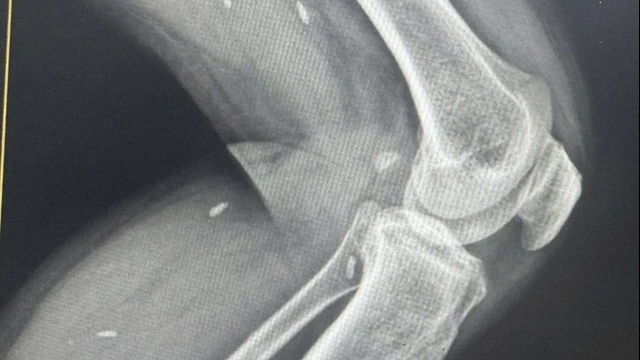

Kết quả chụp X-quang cho thấy người bệnh có dị vật nằm tại phế quản phải. Quá trình nội soi cấp cứu trường hợp trên gặp nhiều khó khăn do dị vật to, trơn, mắc sâu trong phế quản.

| dụng cụ nha khoa bằng kim loại dài 2,5 cm – nghi rơi vào đường thở trong khi làm răng Implant |